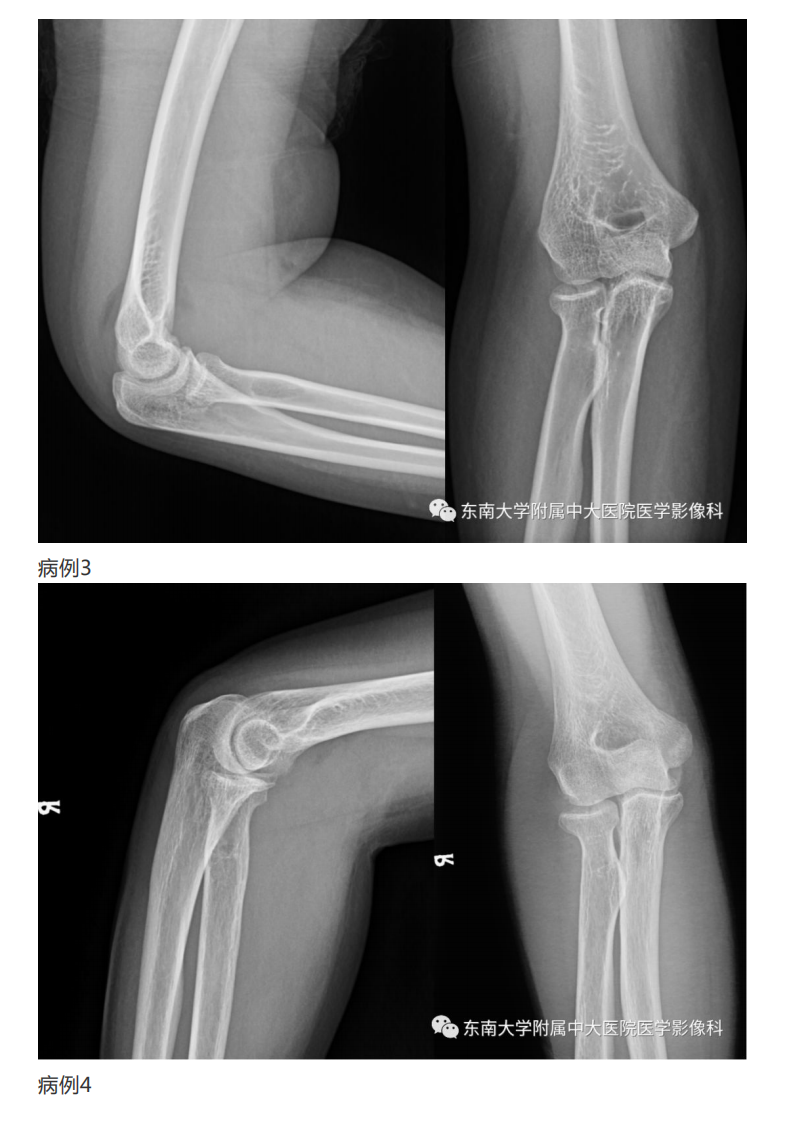

20190409_2【晨读结果公布】2019.04.08肌骨系统疾病.pdf